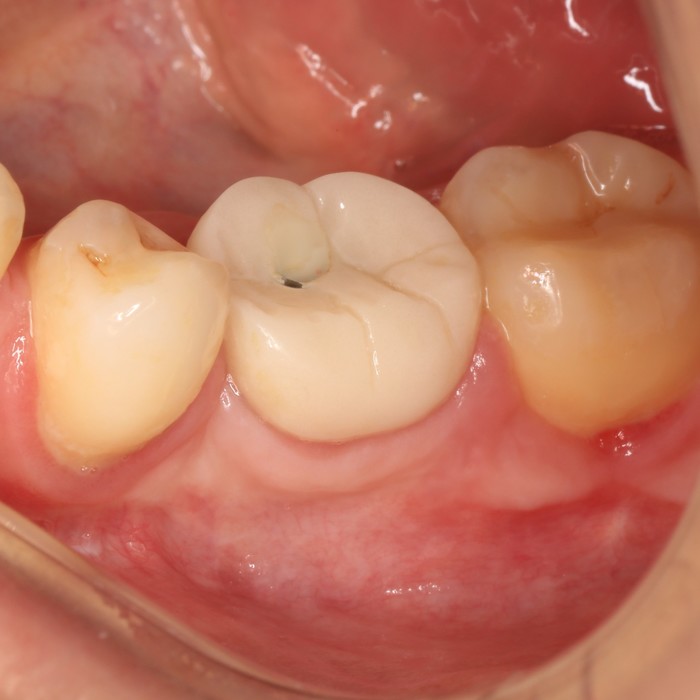

После чистки:

Уже на следующий день была запланирована имплантация.